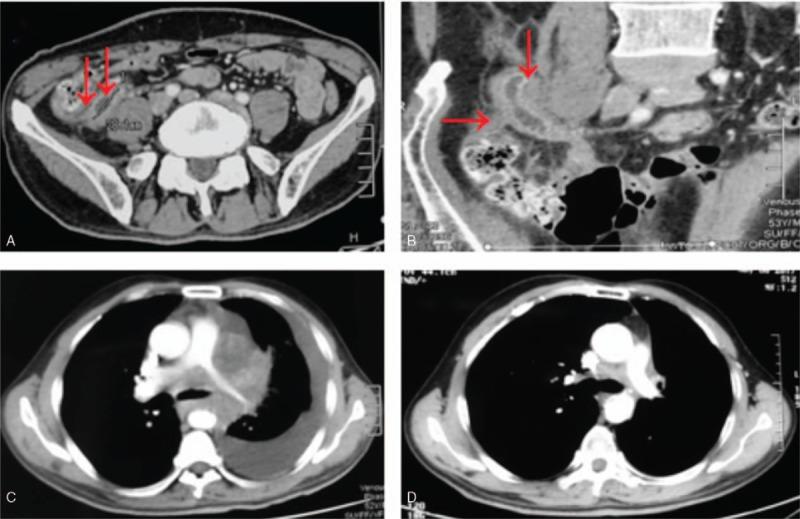

We reported on a 52-year-old man who diagnosed as extensive stage SCLC with abdominal pain for 2 months, aggravated for 2 days.

The patient was diagnosed with extensive-stage SCLC, relapsed with appendix metastasis after treatment by emergency abdominal surgery.